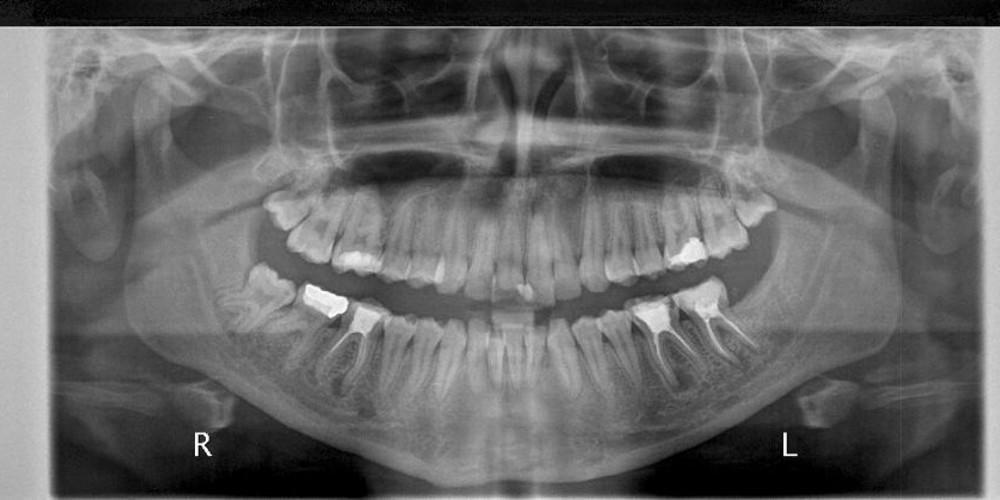

«Ήταν ένας καλοήθης όγκος, τον οποίο αφαιρέσαμε και βρήκαμε ότι είχε μέσα εκατοντάδες δόντια» συμπλήρωσε, περιγράφοντας την επέμβαση, που διεξήχθη τον περασμένο μήνα.

Οι Ινδοί γιατροί πιστεύουν ότι ο αριθμός των δοντιών που βρέθηκαν αποτελεί παγκόσμιο ιατρικό ρεκόρ.